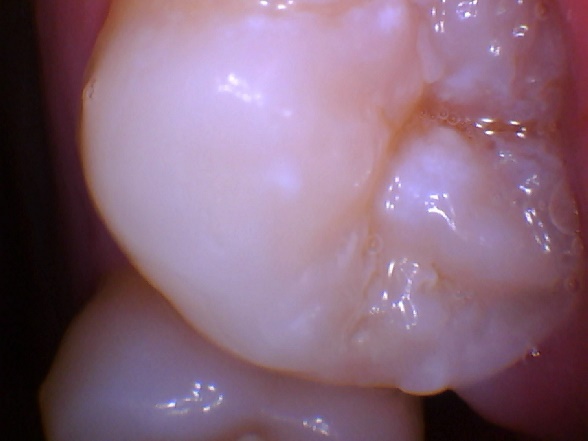

Permanent molars

1st molar

2nd molar